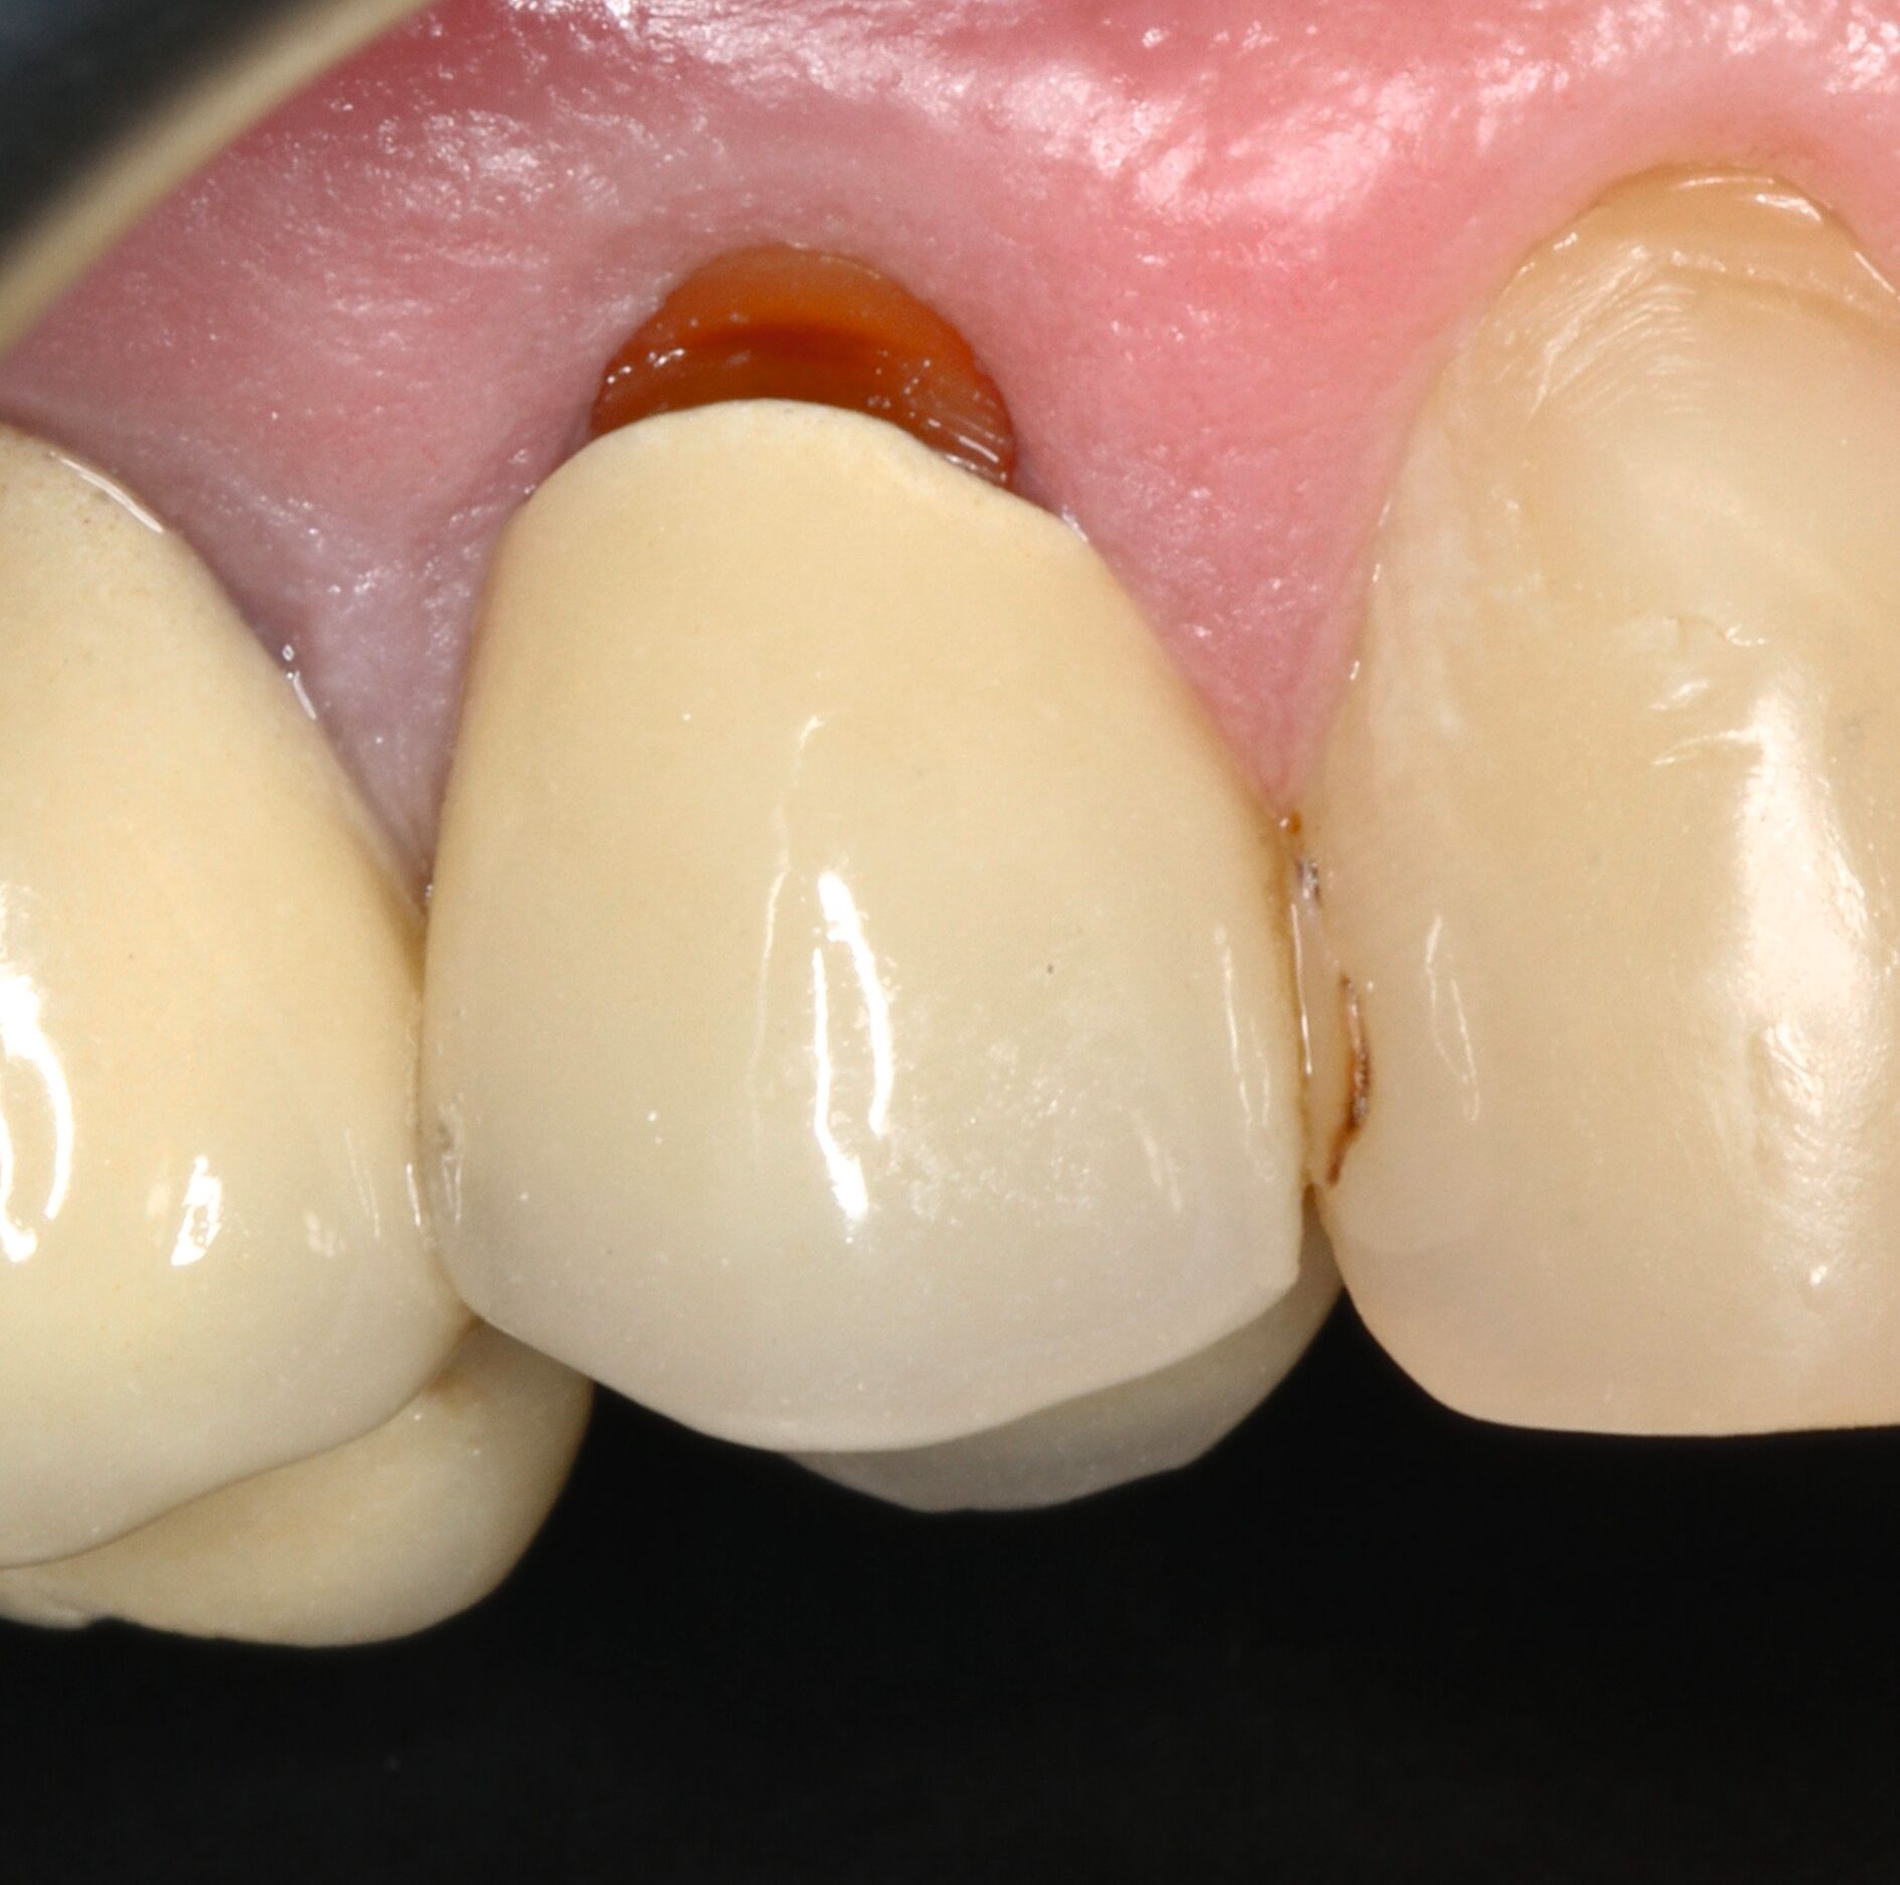

Vor 25 Jahren hatte der Patient ein Frontzahntrauma an Zahn 22 erlitten, der daraufhin mit einer Wurzelspitzenresektion und einer retrograden Amalgamfüllung versorgt worden war (Abbildung 3a). Dabei war die Zahnkrone mit einer keramisch verblendeten Stiftkrone aus Nichtedelmetall rekonstruiert worden, die nun aufgrund von Sekundärkaries insuffizient und gelockert war, jedoch keine Beschwerden verursachte. Klinisch wies der Zahn eine sehr kurze klinische Krone ohne ausreichendes Ferruledesign auf (Abbildung 5a) [Naumann et al., 2018a; Naumann et al., 2018b]. Neben dem Verdacht auf einen obliterierten mittleren Wurzelkanalabschnitt gab es röntgenologisch keinen Hinweis auf apikale Osteolysen oder parodontale Auffälligkeiten (Abbildung 3b). Der Patient entschied sich trotz des erhöhten Zahnhartsubstanzdefekts für den Zahnerhalt durch einen adhäsiv verankerten Kompositaufbau.

Für die restaurative Therapie von Zahn 22 wurde die alte Stiftkrone entfernt und die Stiftbohrung an die neue Indikation angepasst (Abbildungen 5a und 5b). Die Zahnkrone wurde dabei in drei Phasen wiederhergestellt: adhäsives Zementieren eines konfektionierten Glasfaserstifts, Stumpfaufbau und Modellation einer direkten Kompositkrone mit Silikonschlüssel, Frontzahnmatrize für komplexe Situationen und Schneepflugtechnik (Abbildungen 5c bis 5e) [Urkande et al., 2023; Amaro et al., 2021; Frese, 2020; Mannocci et al., 2002; Dimitrouli et al., 2011; Opdam et al., 2003]. Im Röntgenkontrollbild zeigt sich ein suffizienter Stiftaufbau (Abbildung 6).